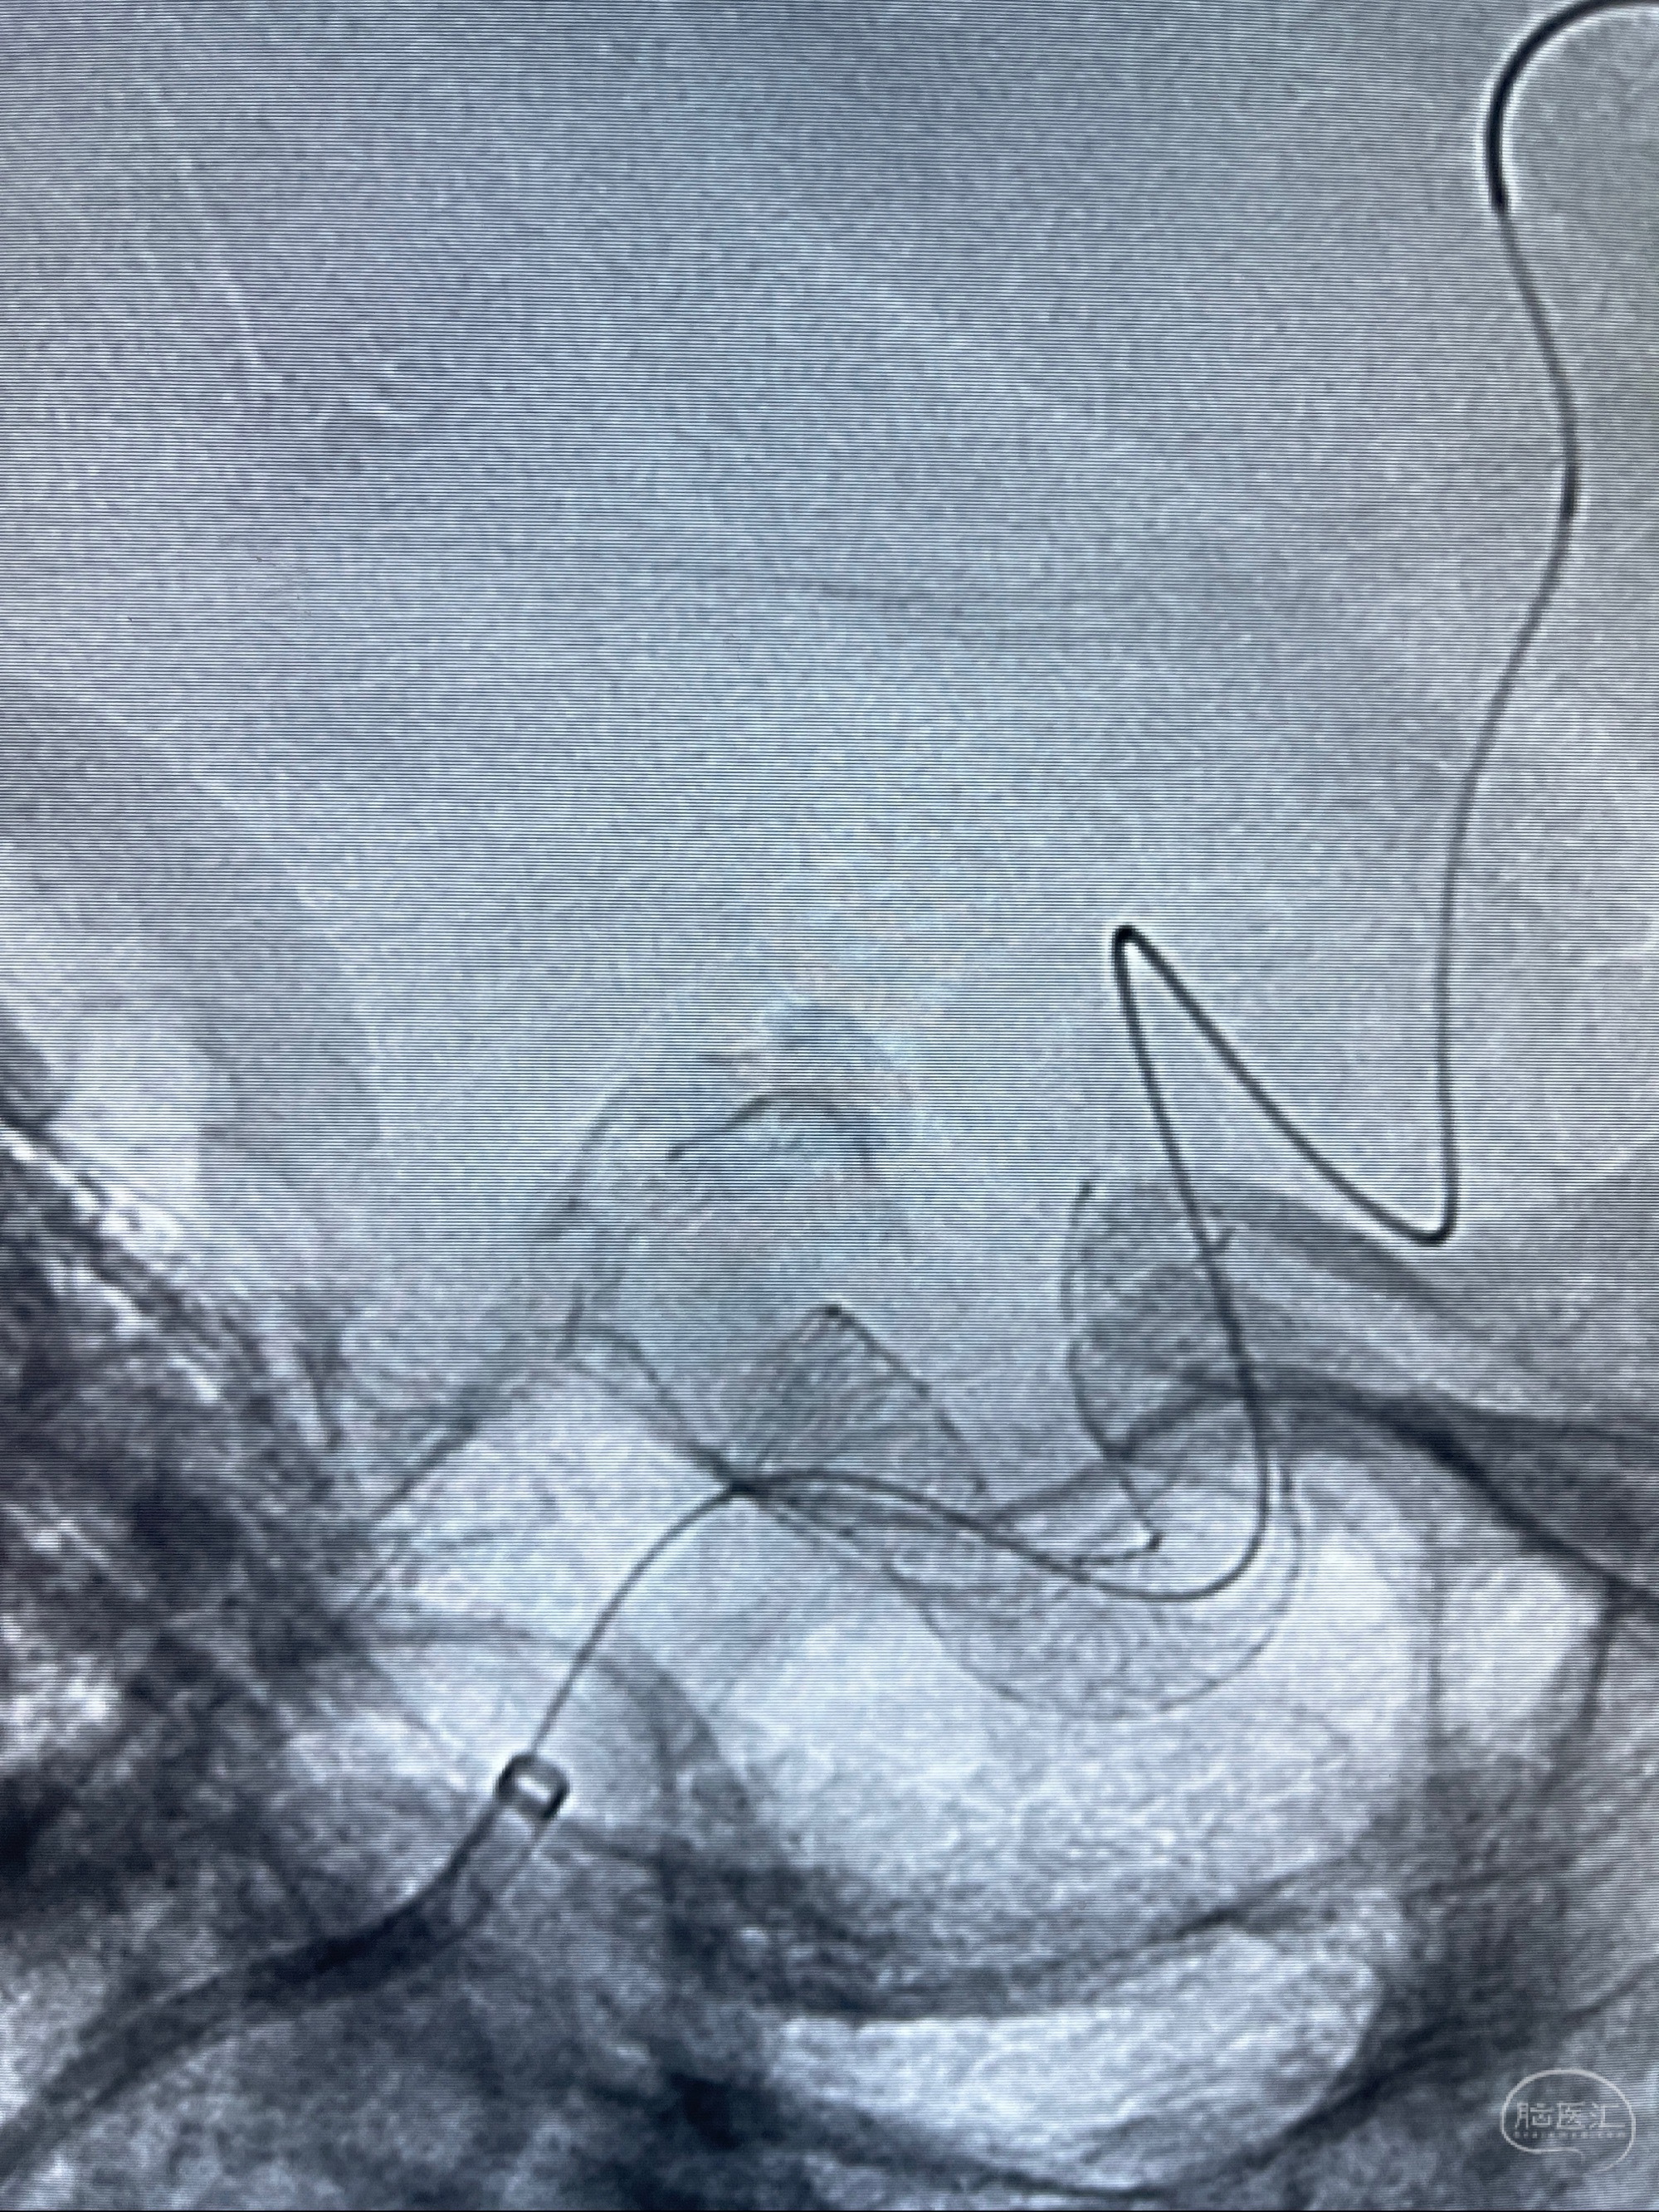

2023-08-01全麻下行双侧颈眼动脉瘤支架辅助栓塞

- pipeling4.5-20mm

- pipeline 4.0-20mm